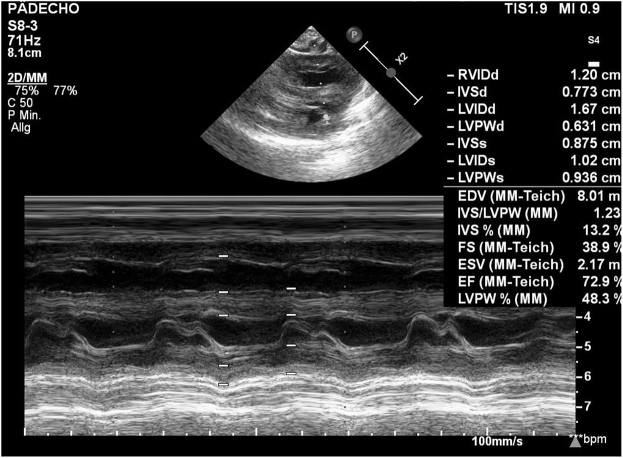

Case presentation: We report a rare case of excessive neonatal weight in a medically unsupervised pregnancy and give a literature review on this significant subject. A 38 year-old woman (Gravida 8 Para 7) presented herself at 42 2/7 weeks of gestation at the labor ward. The pregnancy had not been supervised medically. Labor induction was initiated. Due to failure to progress and suspicion of a disproportion of the fetal head and maternal pelvis an urgent caesarean section was performed. A morbidly macrosomic male infant was delivered (birth weight: 6,760 g [>99. percentile], length: 60 cm [>99. percentile]).